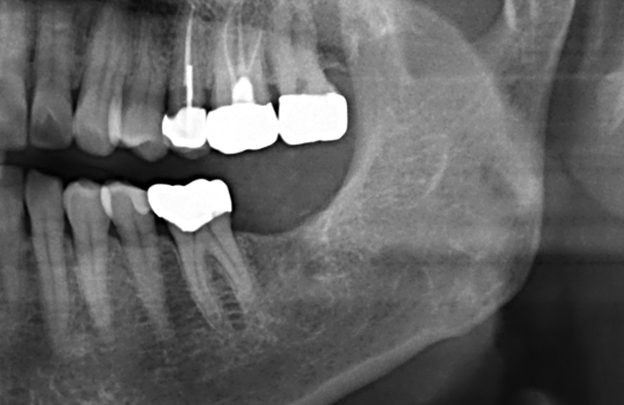

발치 즉시 식립 증례

BEFORE

AFTER

임플란트 촬영날짜: 2021-12-31

임플란트 촬영날짜: 2021-11-09